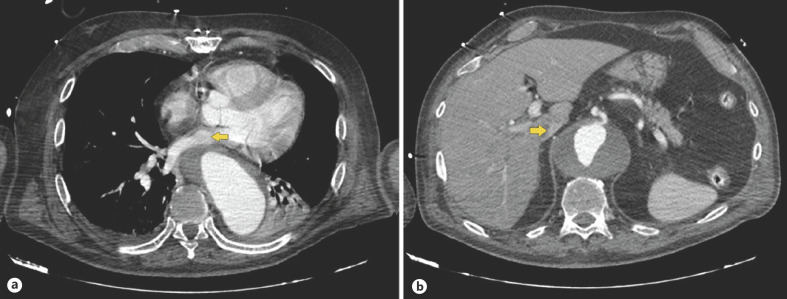

Dysphagia Aortica: An Uncommon and Potentially Life-Threatening Condition.

大动脉吞咽困难:一种不常见且可能危及生命的疾病。